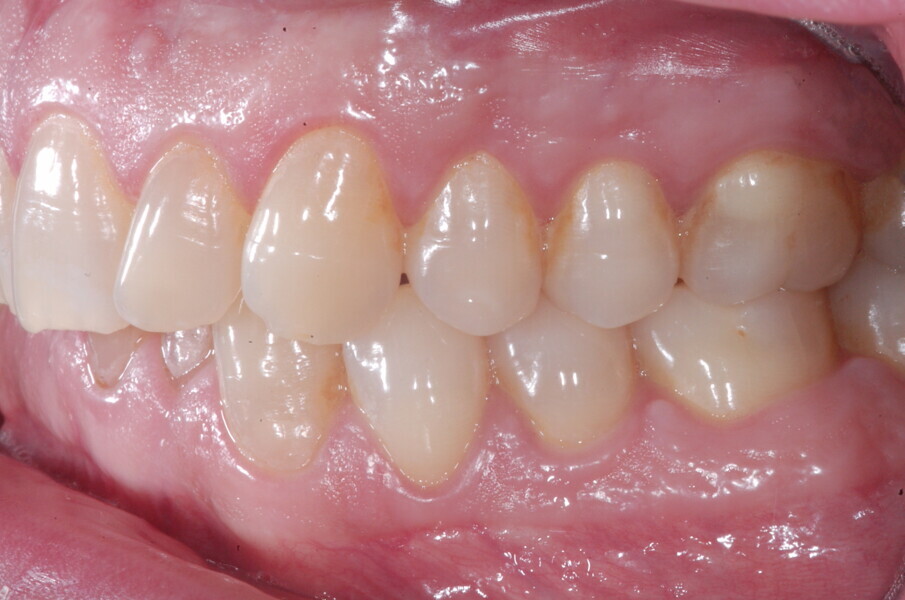

À la fin du traitement, on pouvait observer une relation de classe I des canines et des molaires, une légère augmentation de l’inclinaison des incisives supérieures (Ui-FH = 112°), une correction complète de l’inclinaison des incisives inférieures (IMPA = 97,09°) grâce à la vestibulo-version, et une légère amélioration de l’hypodivergence (SN-GoGn = 27°) résultant de l’extrusion relative des dents postérieures, et de l’utilisation d’élastiques de classe II — petite variation (1°) très intéressante compte tenu de l’âge du patient (Figs. 25–35). La ligne du sourire était harmonieuse et correspondait à une relation idéale entre les incisives supérieures et la lèvre inférieure. Le sourire avait été élargi grâce au contrôle du torque des segments latéraux et postérieurs.

La ligne du sourire était harmonieuse et correspondait à une relation idéale entre les incisives supérieures et la lèvre inférieure. Le sourire avait été élargi grâce au contrôle du torque des segments latéraux et postérieurs. La superposition des tracés céphalométriques montrait des changements intéressants induits par le traitement orthodontique (Figs. 36 et 37) :

Lors du suivi à un an, alors que le patient portait un appareil de rétention (appareil de rétention Vivera avec rampes d’occlusion, Align Technology), le résultat était stable et l’intercuspation était nettement meilleure (Figs. 38–42).